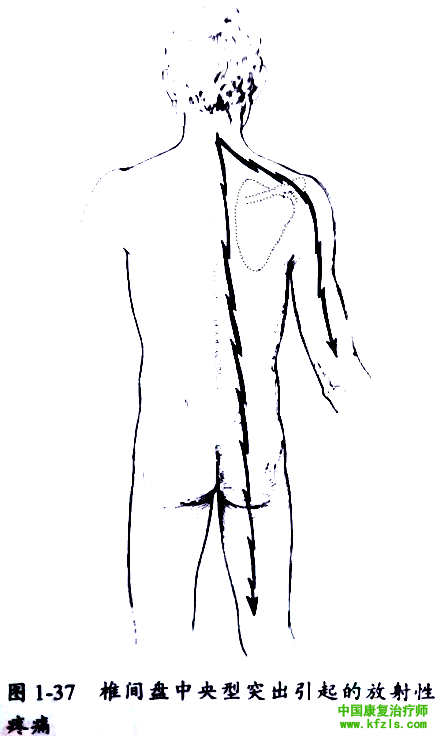

椎间盘突出引起的症状与突出的部位有关。常见是椎间盘向侧方突出,直接压迫于神经根上,造成明显的根性症状。如椎间盘为中央型突出,可引起上臂和腿部症状(图1-37 )。